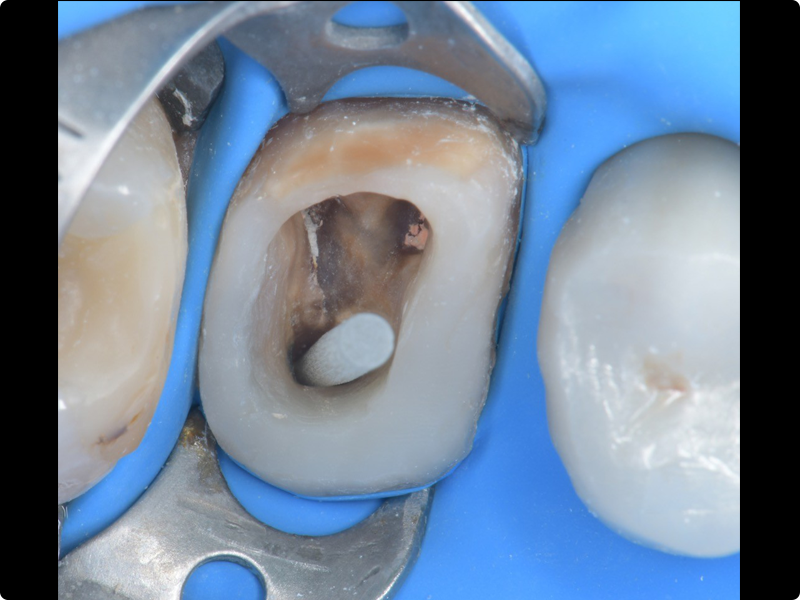

Endodonzia con la sistematica FQ di Komet + Cemento Bioceramico

• Principi e applicazioni della sistematica FQ in situazioni cliniche differenti (canali facili, medi e complessi)

• Le differenti tecniche di otturazione canalare.

• Introduzione al cemento bioceramico: caratteristiche, vantaggi clinici del BioSeal di Komet

• Come integrare il BioSeal nella tecnica di otturazione canalare: protocolli, gestione del cono di guttaperca, detersione, indurimento e prevenzione dell’estrusione

• Sessione pratica su simulatori: utilizzo della sistematica FQ + sperimentazione pratica dell’otturazione canalare con cemento bioceramico